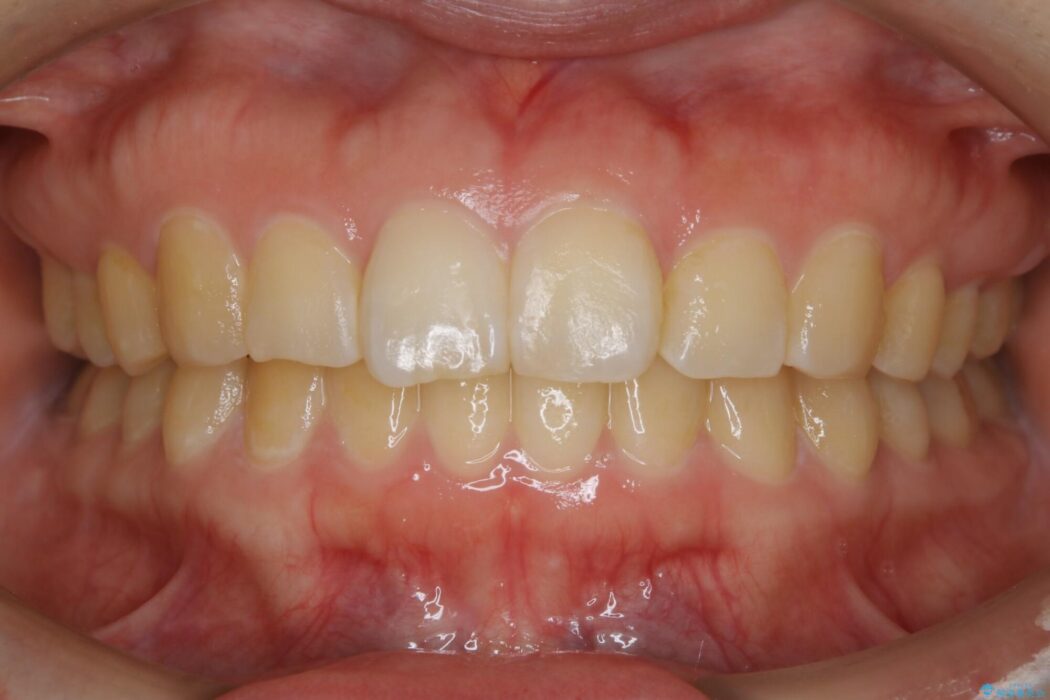

治療後について

咬合調整は咬合力を複数の歯に均等に分散することで歯の負担を少なくでき、歯の長持ちに繋がります。

噛み合わせが改善されたことによりしっかり噛めるようになったと喜んでいただきました。